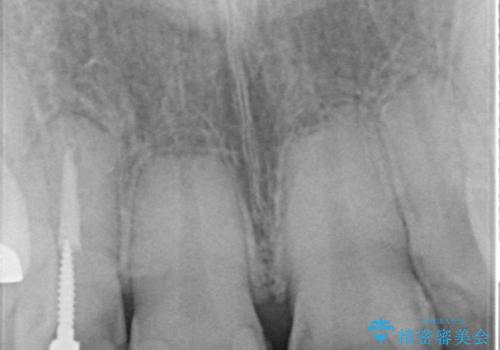

- 前歯の見た目を主訴にご来院された患者様です。虫歯治療を複数回繰り返して、前歯のつめものがつぎはぎになっていました。

当初は1番目立つ1本だけをご希望でしたが、相談の結果、隣の歯(神経が抜いてあり金属が入っている歯)と2本同時に製作することになりました。

患者様は前歯の見た目の改善を主訴にご来院されました。上の前歯6本とも古いつめものがつぎはぎになっていましたが、まずは1番目立つところを治すことをご希望でした。相談の結果、今回は2本できれいになるように工夫しました。